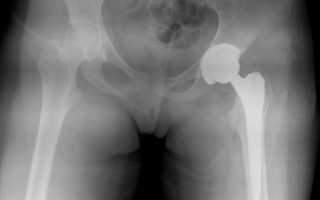

Пациента с такой травмой направляют на рентгенологическое обследование. При выявлении вывиха проводится закрытое вправление головки эндопротеза. Операция проводится под анестезией. После вправления человеку рекомендуется соблюдать постельный режим в течение 1 дней. Обездвиживание поврежденной конечности производится с помощью гипсовой повязки.

При отсутствии осложнений пациенту назначают процедуры лечебной физкультуры. На основании рентгенологических снимков специалисты выявляют степень износа элементов имплантата. При вывихе происходит смещение головки эндопротеза относительно чашки. Кроме того, рентгенологическое обследование позволяет определить симптомы остеолиоза.